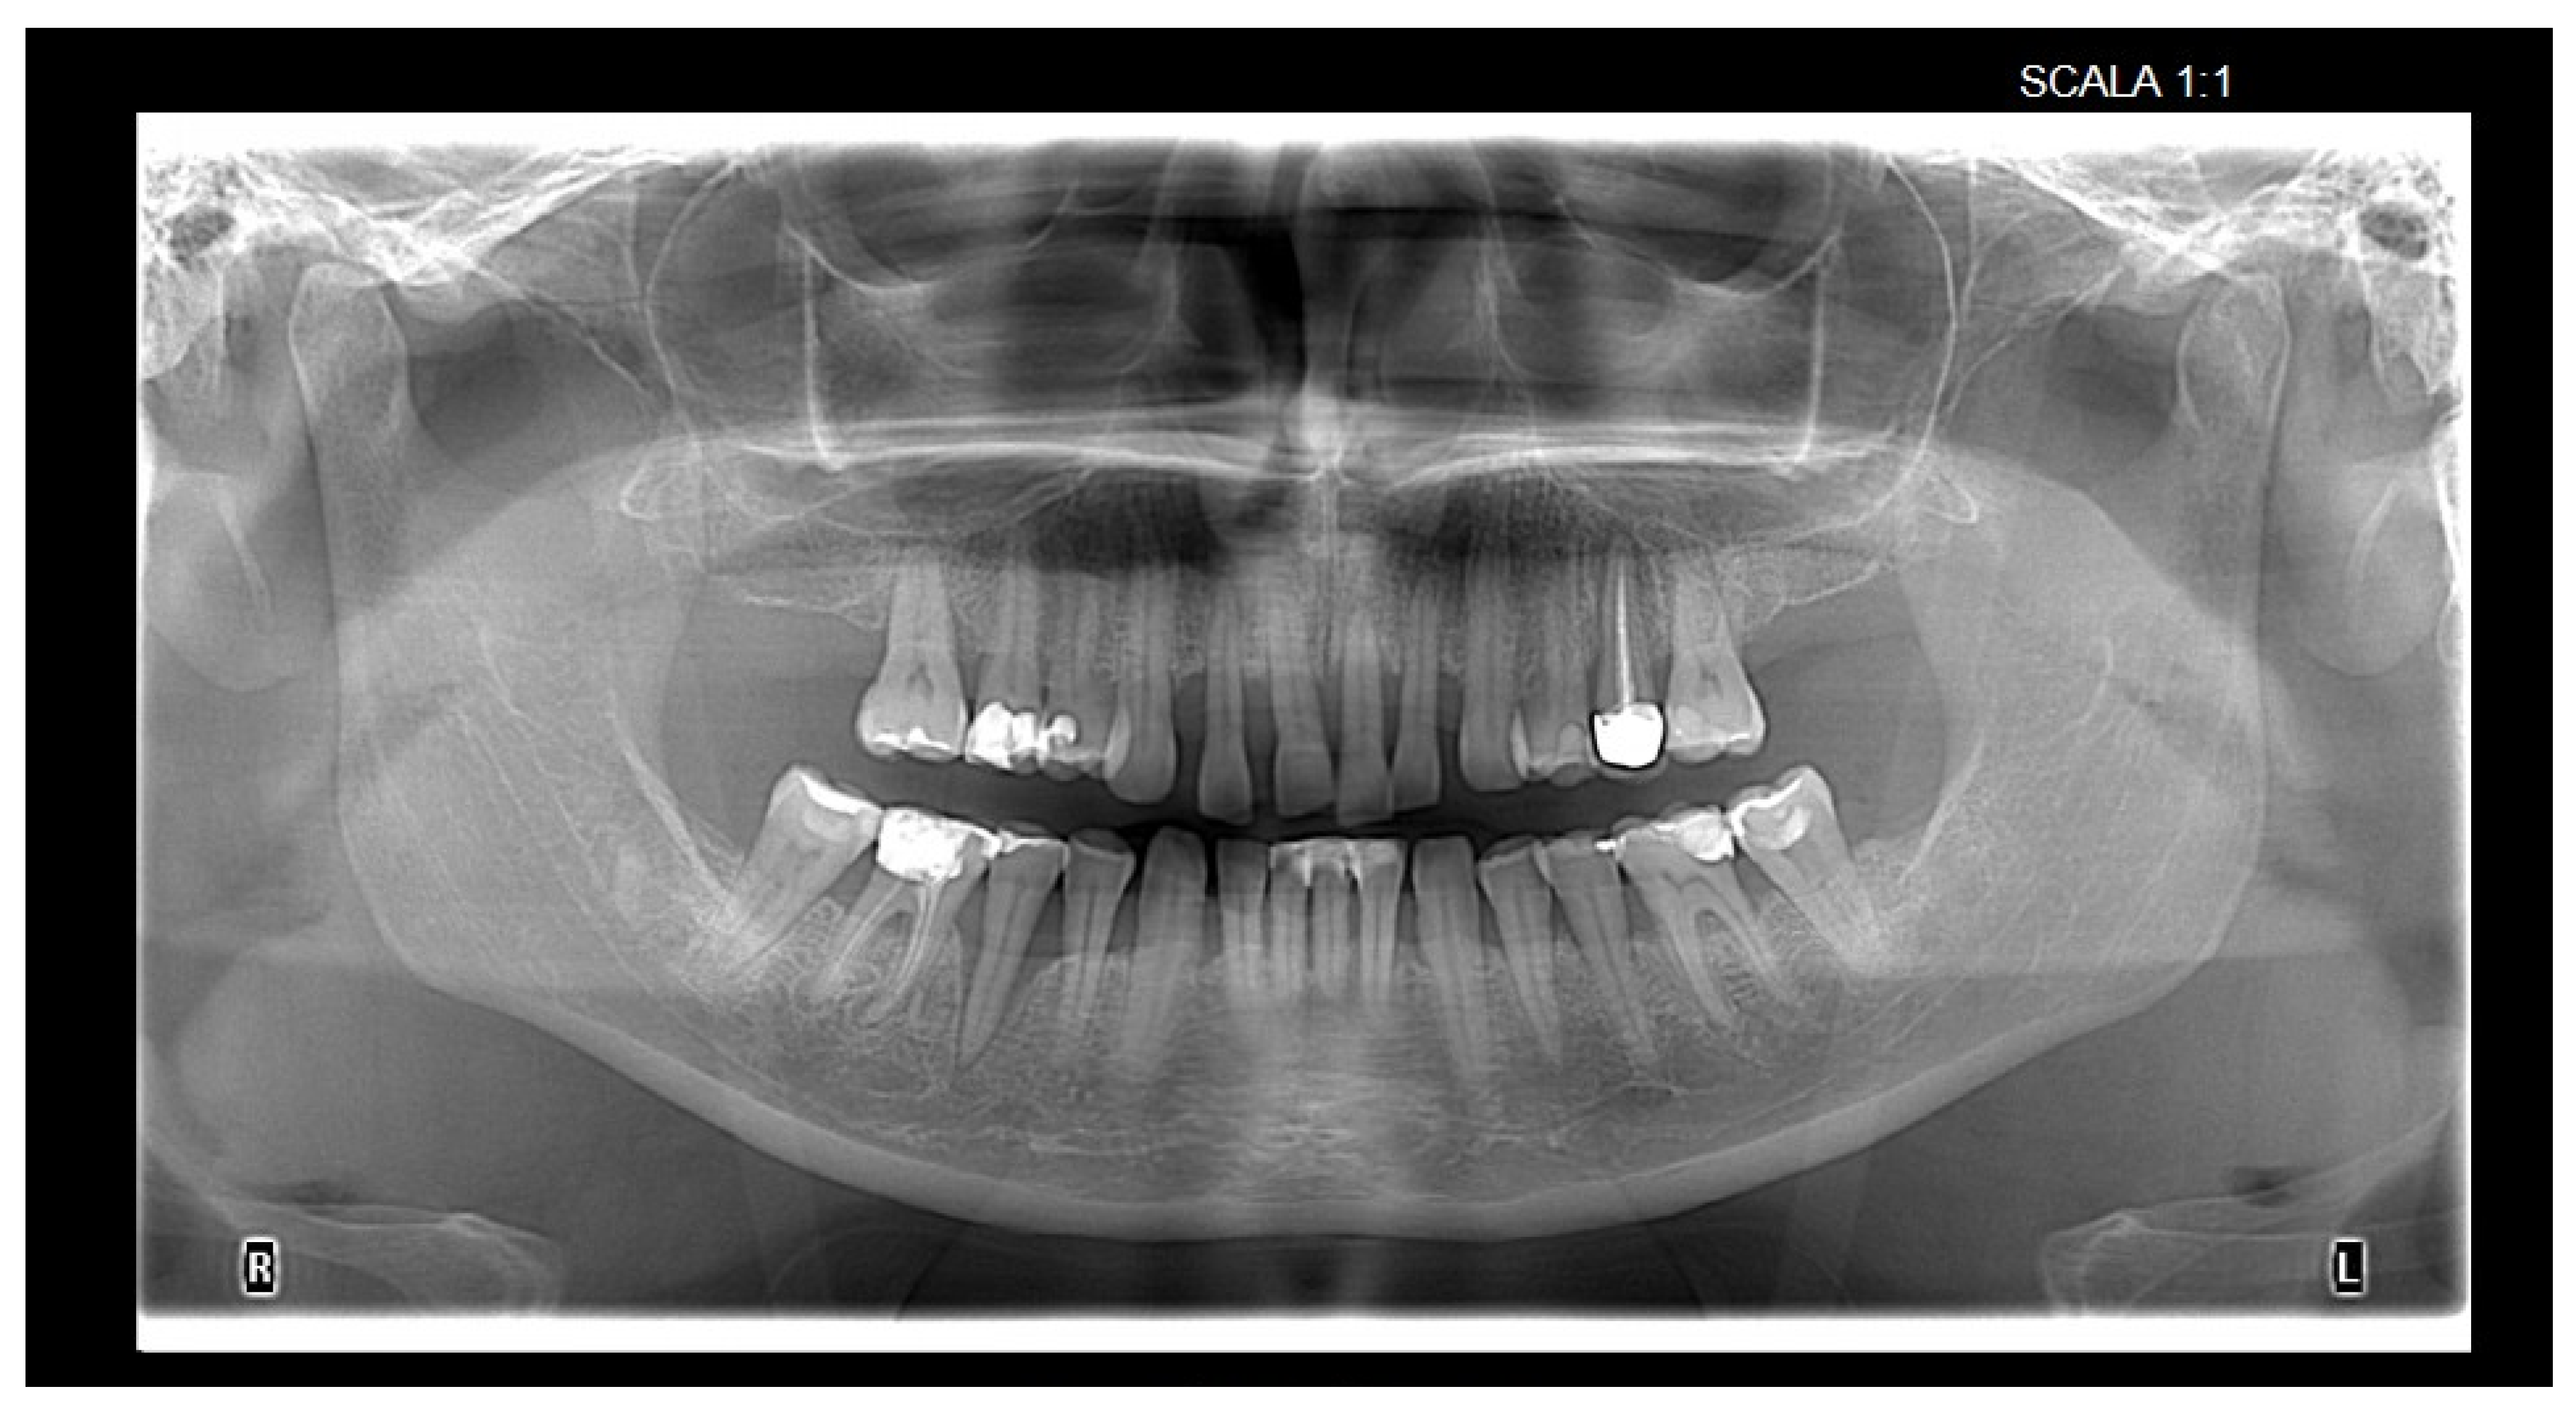

| Alveolar bone loss Rx (mean) | 1.59 mm | 1.15 mm | 1.25 mm | <0.001 1 | 0.003 | 0.037 | >0.999 |

| Widening of periodontal space (n, %) | N = 52; 11% | N = 30; 7% | N = 31; 7% | 0.005 2 | 0.012 | 0.018 | >0.999 |